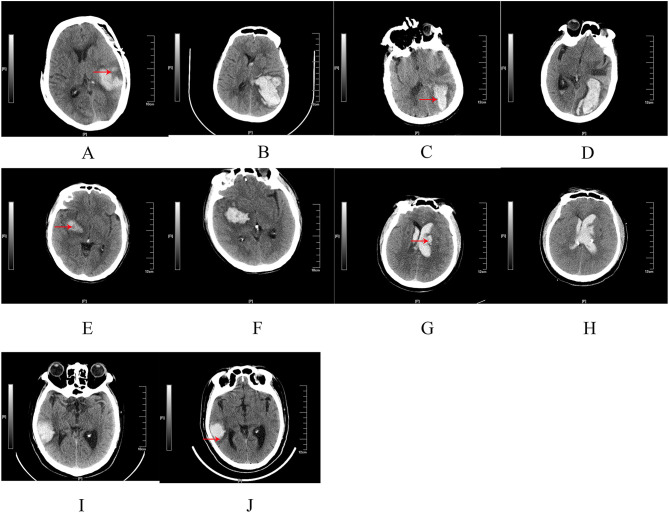

Results: Hematoma expansion was associated with diabetes mellitus, a low Glasgow Coma Scale (GCS) score at admission, elevated systolic blood pressure at admission, coagulation abnormalities, and specific computed tomography (CT) imaging findings, such as heterogeneous density, black hole sign, swirl sign, lobulation sign, and blend sign. A prognostic model incorporating these factors demonstrated robust predictive performance, achieving an area under the curve of 0.771 (95% CI: 0.628-0.915, p = 0.002). The model yielded a maximum Youden index of 0.489, with an optimal cutoff score of 38, a sensitivity of 54.5%, and a specificity of 94.4%. Mortality among individuals with coagulation abnormalities was 53.3%.

Conclusion: Coagulation abnormalities, GCS score, systolic blood pressure at admission, CT imaging findings, and diabetes mellitus were identified as predictors of hematoma expansion in spontaneous ICH. Individuals with coagulopathy and elevated systolic blood pressure at admission exhibited the poorest prognoses.